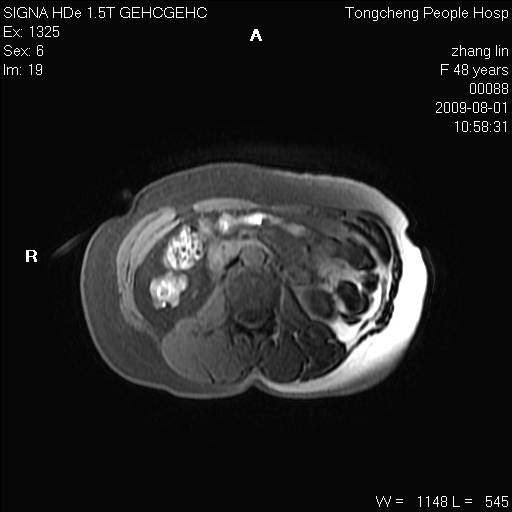

女,48岁。健康体检,彩超发现右肾占位性病变。平素健康。

临床诊断:右肾占位性病变,性质待定(囊肿?肿瘤?)。

上中腹部mr平扫+增强扫描,图像如下:

右肾上极见一类圆形病灶,t1wi呈等信号t2wi呈等高混杂信号,三期增强无强化,边界清---考虑囊肿出血。

同反相位均表现为等信号,病变无强化,考虑含蛋白的囊肿可能,弥散加权相或许有些帮助,